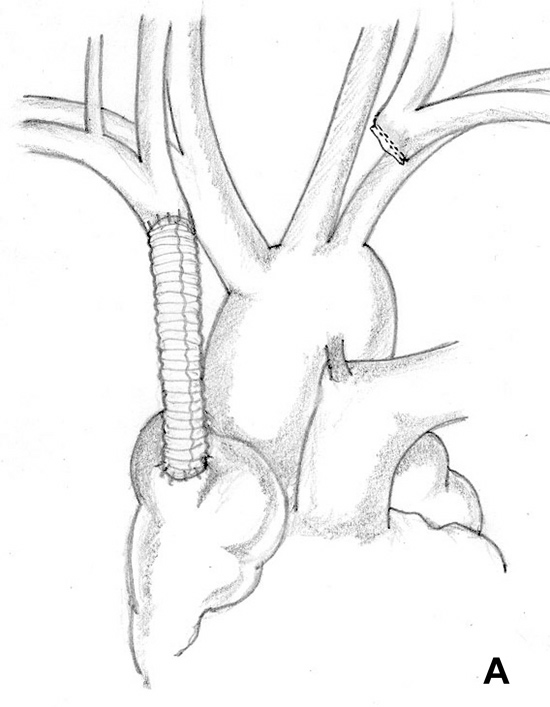

Figure 12. Reconstruction of the left brachiocephalic vein using a ringed PTFE graft. Figure 13. Simultaneous reconstruction of the right and left brachiocephalic system.

SVC replacement: replacement of the whole body of the SVC is the most frequent type of reconstruction (Figure 8). In patients with lung cancer, it is usually associated with right upper lobectomy or pneumonectomy; however, SVC reconstruction may be required during carinal pneumonectomy, sleeve lobectomy (Figure 9), and reconstructive procedures of the pulmonary artery[5]; the latter two should always be attempted if they help to avoid pneumonectomy. SVC replacement requires a tumor–free confluence of both brachiocephalic veins. The reconstruction is usually performed using a straight non-ringed PTFE graft (18 – 20 mm). An autologous or bovine pericardial tube could also be used (Figure 10). After proximal and distal clamping, the SVC is excised. The proximal anastomosis is performed first, using a 5-0 polypropylene suture, starting from the posterior aspect of the prosthesis or the tube of pericardium. The distal anastomosis is subsequently performed with the same technique. Before tying the distal suture line, the proximal clamp is gently released and deaeration is performed; afterwards, the distal clamp is released and knots are tied. After complete filling of the graft by blood, there should be no tension of the suture lines or torsion or kinking.

Sometimes it may be indicated to replace only one brachiocephalic vein (either the right or left, according to local invasion). A ringed PTFE graft should be used (Figure 11, 12), especially for the left vessel and the distal anastomosis should be performed on the inferior stump of the SVC or on the right atrium. Use of the auricle should be avoided because of the presence of the pectinate muscles. In this situation, the prosthesis may be too long after closure of median sternotomy and could kink easily. Also postoperative mediastinal fibrosis (especially if radiotherapy is administered) could contribute to graft compression. Simultaneous revascularization of both brachiocephalic veins (Figure 13) is rarely required since there are enough anastomotic venous communications in the neck. Revascularization of both systems is indicated in case of previous neck surgery (laryngeal or thyroid surgery for cancer); a separate distal anastomosis of the two grafts is preferred to avoid thrombosis of the accessory left limb of a Y graft, starting at the level of the graft–to–graft anastomosis.